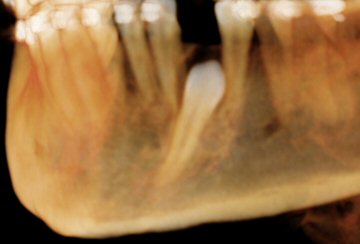

Fig. 16 CBCT: showing impacted lower left canine (at 18 y.o.)

© Copyright 2007-2014, Vu Orthodontics. All rights reserved.